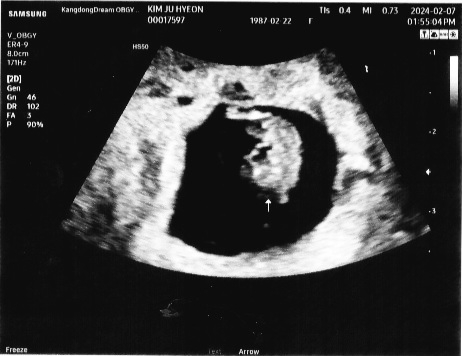

7주 3일 드뎌 심소 듣고왔어용~~

5주2일에 보러갔을땐 아기집이 세로로 길쭉해서 걱정 좀 했었는데 오늘 보러가니 넓직하게 커졌네용 ㅎㅎ 2주가 어찌나 길던지~~ 심장소리도 아주 우렁차더라구요 눈물 쏙 뺐네요ㅜㅜ 심장 : 161bpm CRL : 1.21cm 처음에 배로 봤다가 자궁이 뒤에있다고 안보인다하셔서 다시 옷 갈아입고 질초음파로 봤잖아요ㅋㅋ 똥배땜에 안보이는줄 알고 당황당황..;; 유산기도 없고 아주 건강하다고 하셔서 이제 안심하고 마음 편히 설에 임밍아웃해도 되겠어요~ 크 ~ 넘넘 행복하네용😍😍